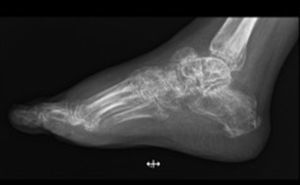

Caso clínicoPaciente mujer de 57 años de edad, que inicia cuadro clínico con sangrado transvaginal y dolor pélvico, por lo cual acude a valoración, se realizan estudios de extensión, entre ellos ultrasonido y toma biopsia endometrial, con reporte de AE y, por lo tanto, se le realiza histerectomía, linfadenectomía pélvica bilateral y paraaórtica con reporte histopatológico de adenocarcinoma endometrial de tipo endometrioide moderadamente diferenciado (G2), que infiltra a 0.1cm de la superficie serosa del útero, con extensión a ambos parametrios, con permeación linfovascular presente, sin evidencia de lesión en márgenes quirúrgicos, adenopatías negativas (EC II FIGO), por lo que recibe tratamiento con radioterapia externa 50.4Gy y braquiterapia intracavitaria. Durante su seguimiento, a 6 meses de terminado el tratamiento, refiere dolor intenso y edema en tobillo izquierdo, así como incapacidad para la deambulación. En las radiografías solicitadas observamos disminución en la densidad ósea de los huesos del tarso, y alteración en la morfología del hueso astrágalo (fig. 1). La tomografía axial computarizada de dicha región muestra lesión lítica expansiva de predominio en astrágalo con extensión a partes blandas y huesos del tarso (fig. 2), PET-CT con 18F-fluordesoxiglucosa (FDG) con actividad tumoral a nivel de hueso astrágalo izquierdo con lesión lítica expansiva y afección de tejido blandos adyacentes (fig. 3). Por tal motivo se le realiza biopsia de astrágalo con reporte histopatológico de AE moderadamente diferenciado metastásico (fig. 4). Se inicia tratamiento con radioterapia 30Gy en 10 fracciones, se difiere el apoyo y quimioterapia paliativa con paclitaxel y carboplatino en 6 ciclos, así como aplicación mensual de ácido zoledrónico, hasta completar 6 dosis. Actualmente, a 12 meses de detectada la enfermedad en el astrágalo izquierdo, la paciente presenta buena evolución, sin progresión de la enfermedad y tolerando la deambulación sin dolor (figs. 5 y 6).